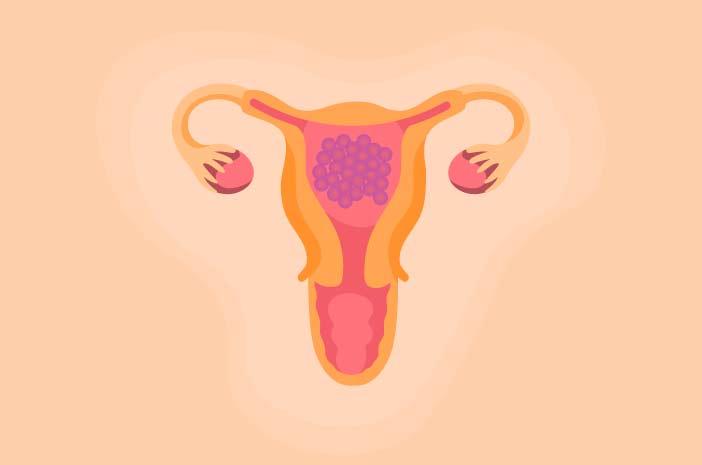

Ini Ciri Ciri Hamil Anggur Yang Perlu Dikenali Sejak Dini

Ini Ciri Ciri Hamil Anggur Yang Perlu Dikenali Sejak Dini